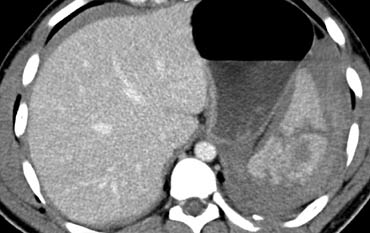

Trước tiên hãy quan sát các hình ảnh bên trái của bệnh nhân bị chấn thương gan.

Các dấu hiệu CT trong trường hợp này là gì?

Các dấu hiệu bao gồm:

- Mất tưới máu hoàn toàn thùy gan phải.

- Vùng ngấm thuốc cản quang (contrast blush) trong nhu mô gan, đồng thời lan ra ngoài bờ bên của gan.

- Tràn máu ổ bụng (Hemoperitoneum).

- Một vùng ngấm thuốc cản quang thứ hai ở mức thấp hơn.